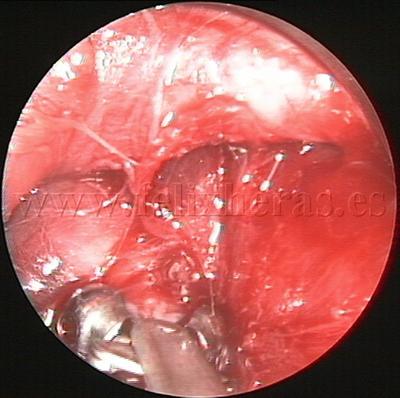

Linfoma cérvico-mediastínico

Biopsia por videomediastinoscopia